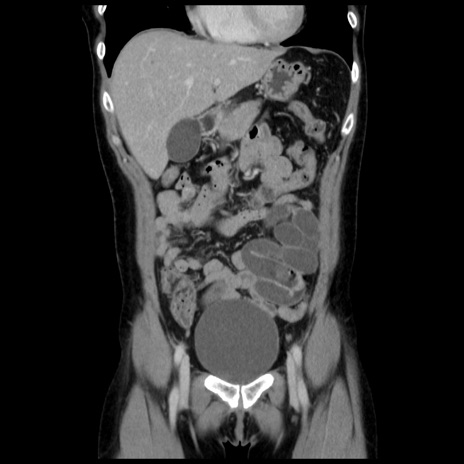

症例10(冠状断像)

【症例】 50歳代女性

【主訴】 腹痛

【現病歴】前日生レバーを食べた。今朝に排便あり。 昼前に突然発症の腹痛を生じ、当院救急外来を受診した。

【既往歴】 子宮筋腫にてで子宮全摘後

【身体所見】 意識清明、腹部:平坦、軟、下腹部やや左を中心に圧痛・反跳痛あり、筋性防御あり

【データ】WBC 7800、CRP 0.07